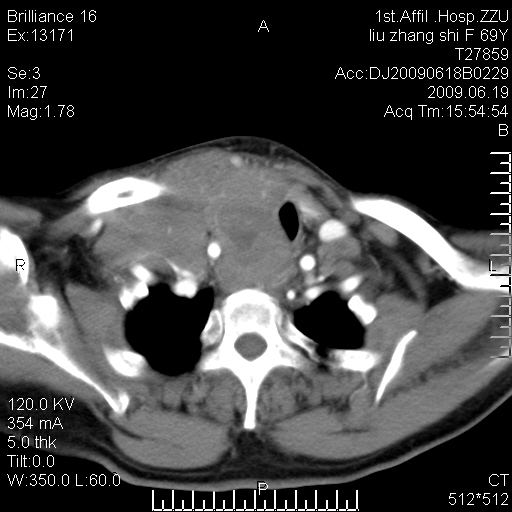

标题: CT26782:女,69岁,颈部占位,3天后公布病理结果。

【病理证实系列】女,69岁,颈部占位,有病理结果,3天后公布。(由于病例时间较久,临床资料不全,请网友见谅)本系列将有几百种常见、少见及罕见病例,均经病理证实。病例资料来自郑州大学第一附属医院。与网友共享,本人有空就发。

甲状腺癌并颈部淋巴结转移。感谢楼主的良苦用心,谢谢。

甲状腺癌并颈部淋巴结转移。

需与鼻咽癌鉴别!

支持甲状腺癌广泛侵及周围结构并颈部淋巴结转移。

鉴别:淋巴瘤、恶性神经源性病变、恶性纤维组织细胞瘤。

病理结果:颈部非霍奇金淋巴瘤。

右侧甲状腺确实有问题